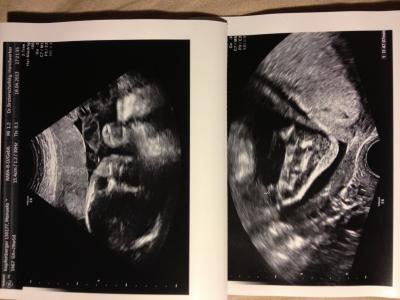

Hallo Mädels, Hatten heute den 3. großen US. Mein Mann, unser Großer (4) und meine Freundin waren dabei und die FA hat alles Super gezeigt und erklärt! Der Kleine ist ein "er" geblieben und alles was man so sehen und sagen kann liegt im normbereich! Er hat mittlerweile 1200 gr und seine Füße sind 4,7 cm! Süß oder?? ;o) hab ein schönes Bild vom Fuß gekriegt! (Anhang) Außerdem hat er momentan ganz oft Turnstunde und lag heut natürlich wieder quer drin :o/ hoffe er dreht sich rechtzeitig noch richtig!! Kann's aber trotzdem nicht Glauben, dass die SS in ca 10-12 Wochen rum is.. Ihr??? Muss jetzt langsam mal anfangen für den süßen alles herzurichten :/ ham noch garnix gemacht.. Aber Montag letzter Arbeitstag.. Dann kann's rund geh!! In diesem sinn.. Gute Nacht euch allen!!